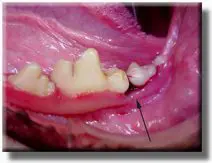

Patient with severe periodontal disease.

Patient before cleaning.

After cleaning, showing exposure of roots and loss of bone. This degree of disease takes years to develop, and could have been prevented with timely treatment.